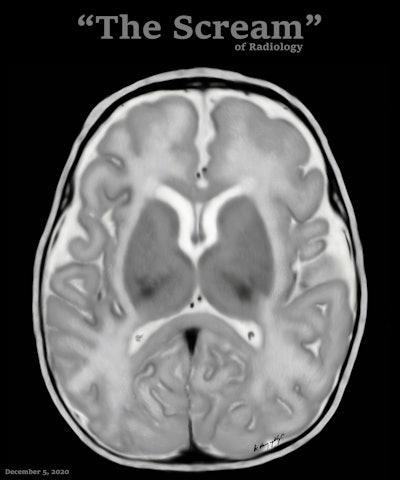

Conceptually, I think it is possible to define the term “radiological illustration” as an emerging discipline that transforms medical imaging data into an aesthetic and didactic narrative. I emphasize that with the motto “pixel by pixel handmade.” I am trying to open a “new path” for the use of visual communication in medical education by trying to combine scientific accuracy in radiological terms with artistic creativity. With this statement, I am trying to express that instead of modifying radiological images, I draw each pixel by hand using technological tools and create a new visual that is both artistically and scientifically original, while remaining faithful to radiological principles.

It’s important to note that radiological illustration should not be confused with medical illustration. The former has yet to be systematically defined in the literature. I believe it deserves recognition as a distinct sub-branch within the broader medical illustration domain.